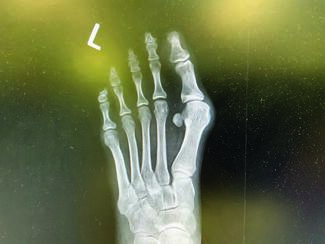

Podiatric surgeons commonly perform procedures for hallux abducto valgus, and capital osteotomies of the first metatarsal are often part of this armamentarium. The technicality of these procedures is relatively straightforward, but...

Over the past decade or so, I have written several articles regarding bunions, their treatment options, including the best surgical option for each type of hallux valgus, and why. The overall solution in my hands for hallux valgus deformity...